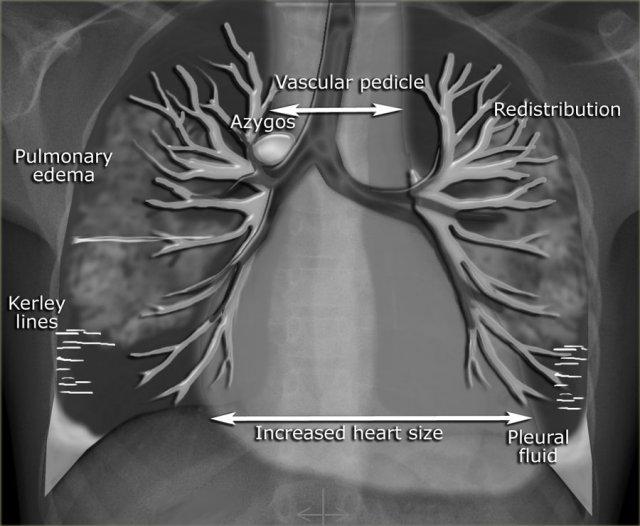

Hình minh họa bên trái thể hiện một số đặc điểm có thể quan sát được trên phim X-quang ngực của bệnh nhân suy tim sung huyết.

Tăng áp lực tĩnh mạch phổi có liên quan đến áp lực mao mạch phổi bít (PCWP) và có thể được phân loại thành các giai đoạn, mỗi giai đoạn có những đặc điểm X-quang riêng trên phim ngực (Bảng).

Hệ thống phân loại này cung cấp một trình tự logic của các dấu hiệu trong suy tim sung huyết.

Tuy nhiên, trong thực hành lâm sàng hàng ngày, một số đặc điểm này có thể không xuất hiện theo trình tự này và đôi khi có thể hoàn toàn vắng mặt.

Điều này có thể gặp ở bệnh nhân suy tim mạn tính, bệnh van hai lá và bệnh phổi tắc nghẽn mạn tính.

Các dấu hiệu sau đây gợi ý suy tim: phù phế nang với đông đặc quanh rốn phổi và dấu hiệu phế quản hơi (mũi tên vàng); tràn dịch màng phổi (mũi tên xanh lam); tĩnh mạch đơn nổi bật và độ rộng cuống mạch máu tăng (mũi tên đỏ) và bóng tim to (đầu mũi tên).

Sau điều trị, chúng ta vẫn có thể thấy bóng tim to, tràn dịch màng phổi và tái phân phối lưu lượng máu phổi, nhưng phù nề đã được giải quyết.